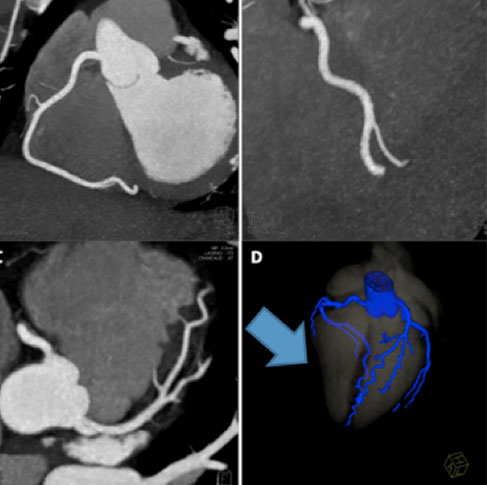

• CORONARY ANGIOGRAPHY

• CT Angiography is the best non-invasive option to rule out any coronary artery disease. It takes only 5 seconds to scan the arteries with the least radiation to the patient & needs no hospitalization.

It has 2 components:

• Calcium Scoring

• Coronary Artery Assessment